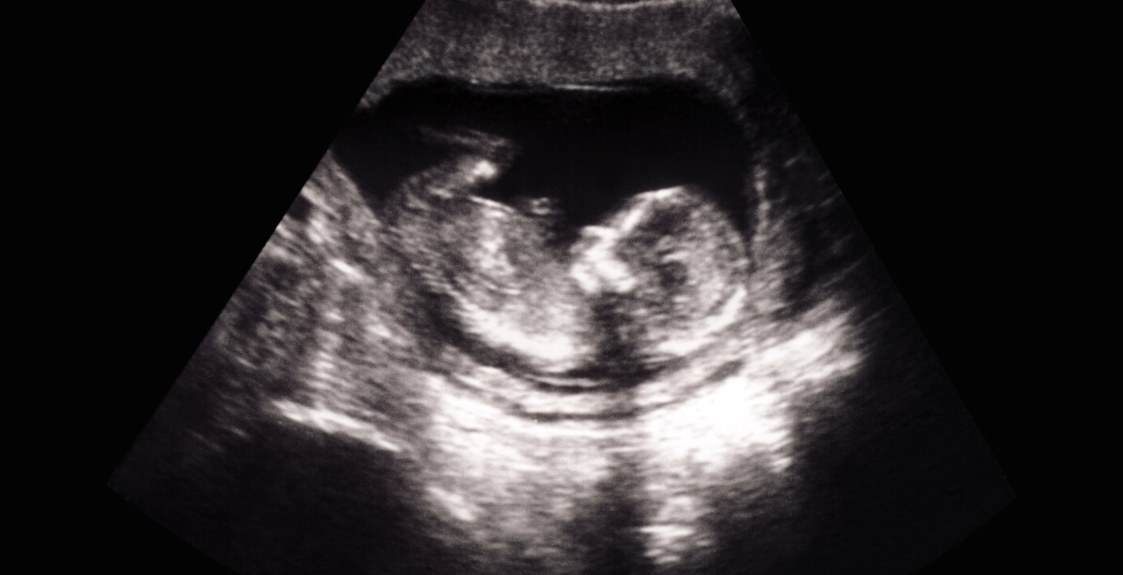

Ultrasound is the primary diagnostic tool for placenta accreta, with most cases identified in the second and third trimesters, although it’s important to know that ultrasound is not perfect. Women and birthing people with a higher risk of placenta accreta – for example, two or more cesarean deliveries with placenta previa – still have considerable risk for placenta accreta even without ultrasound evidence. It is important for both care teams and patients to be prepared that they may encounter placenta accreta at delivery, regardless of ultrasound findings. It is unclear whether MRI adds additional diagnostic value beyond ultrasound, one study found that “MRI confirmed an incorrect diagnosis or incorrectly changed a diagnosis based on ultrasonography in 38% of cases.” In some situations (poor visibility due to scar tissue or obesity, posterior placenta, etc.), MRI can be helpful. Diagnosis of placenta accreta is a critical first step in obtaining proper level care. One study at a placenta accreta center of excellence found that outcomes in expected cases of placenta accreta were better than in cases where placenta accreta was unexpected, even when the diagnosed cases had more severe placental invasion.